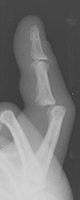

- Click on the image for a larger versionCOblique radiographs of the fourth PIP joint. This demonstrates apparent overriding of the proximal and middle phalanges.